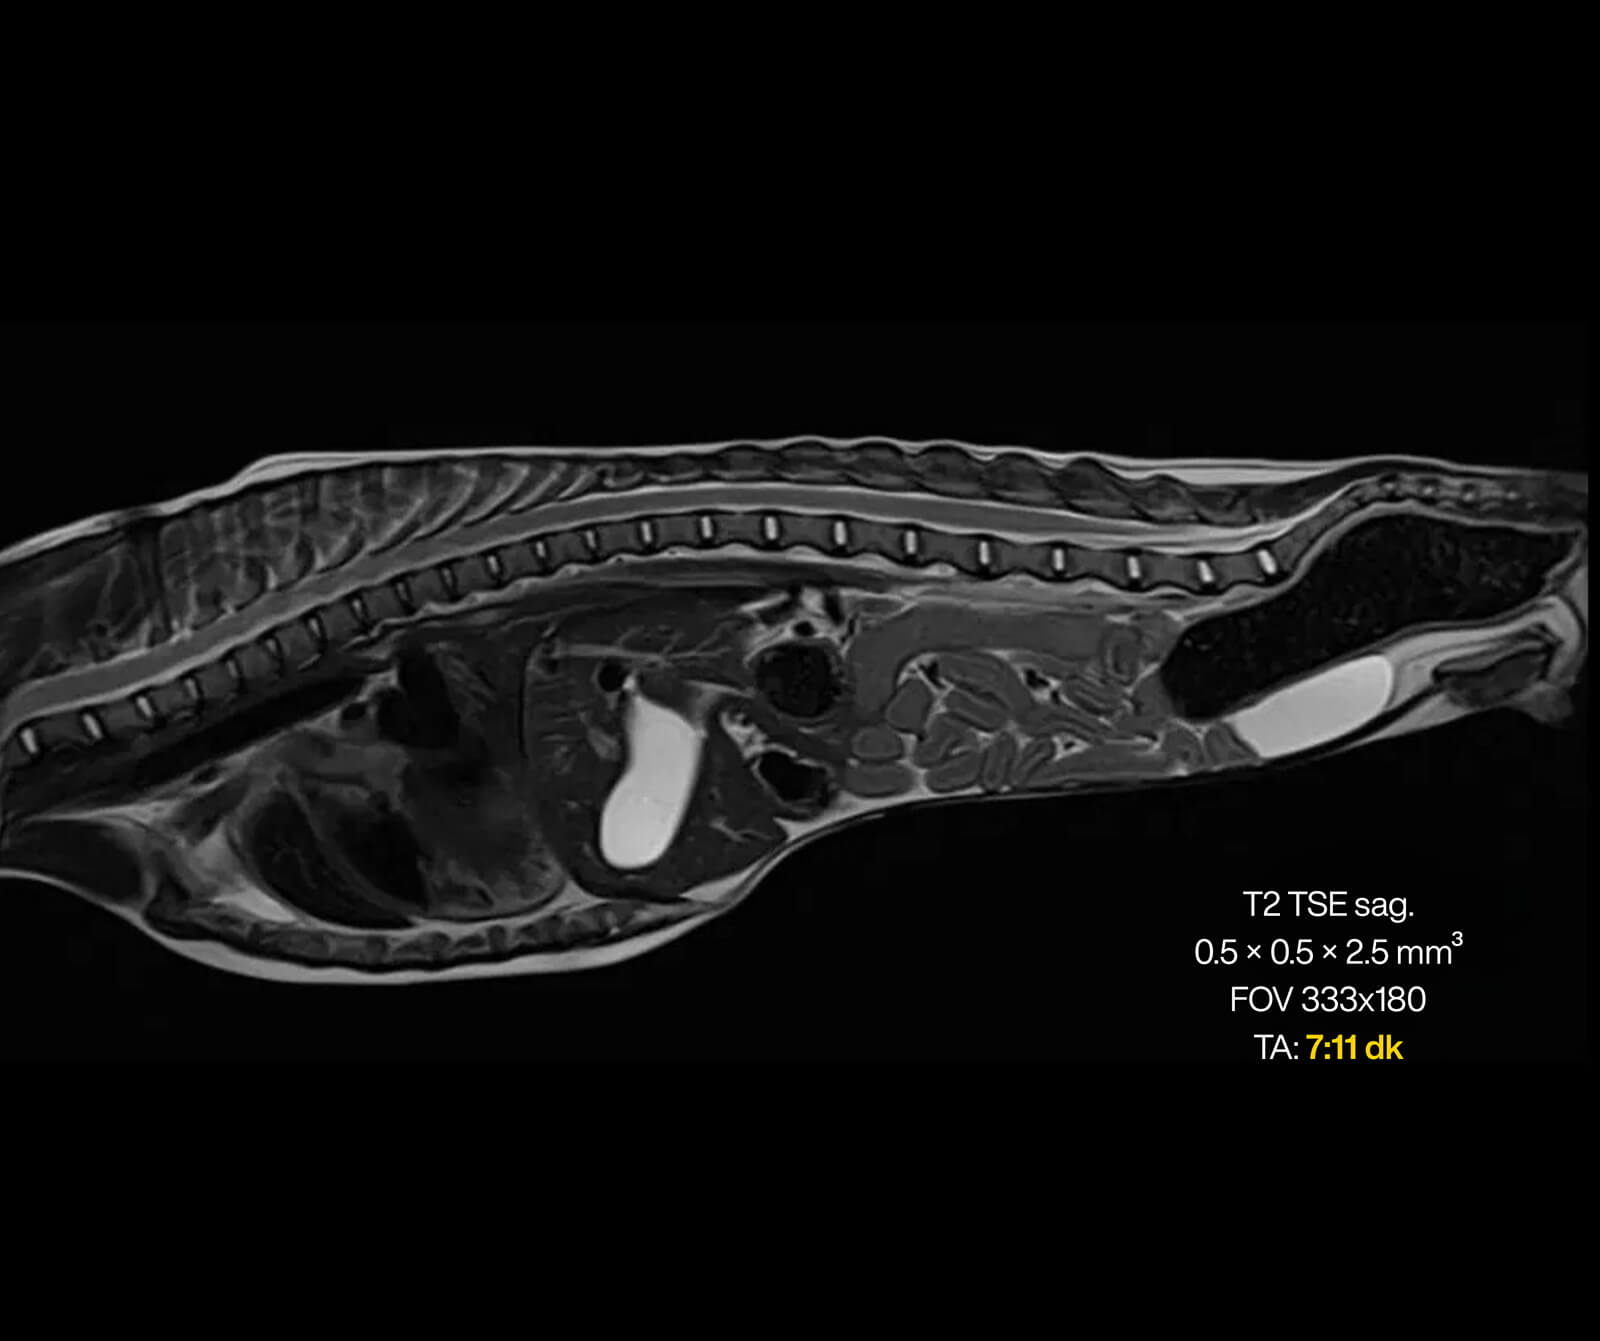

Merkezimizde, süper iletken magnet teknolojisine sahip, yapay zekâ destekli Manyetik Rezonans (MR) sistemleri kullanılmaktadır. Veteriner hekimlik ihtiyaçlarına özel olarak optimize edilmiş bu ileri teknoloji sistemler; yüksek görüntü kalitesi ile hasta güvenliğini birlikte hedefleyen bir altyapı sunar.

Yapay zekâ destekli yazılım ve rekonstrüksiyon teknolojileri, görüntüleme sürecinin planlanması, ham verilerin işlenmesi ve görüntülerin yeniden oluşturulması aşamalarında aktif olarak kullanılmaktadır.

Bu sayede:

• Görüntü gürültüsü azaltılır,

• Kesitsel ve uzaysal çözünürlük artırılır,

• Hareket artefaktları minimize edilir,

• Daha kısa sürede daha yüksek tanısal değere sahip görüntüler elde edilir.

Bu teknolojik altyapı sayesinde geniş görüntüleme alanlarında dahi yüksek çözünürlük ve detaylı kesitsel görüntüler sağlanırken, sevimli dostlarımızın anestezi altında geçirdiği süre optimum düzeyde tutulur ve tanısal doğruluk en üst seviyeye çıkarılır.